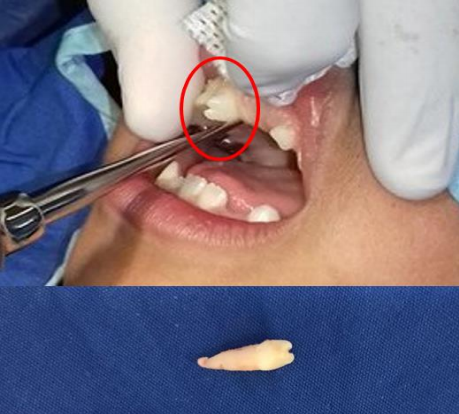

El manejo de los dientes supernumerarios igualmente depende del tipo y posición del diente. Generalmente la remoción inmediata del mesiodens está indicada cuando existe inhibición o retraso de la erupción, desplazamiento de los dientes adyacentes, interferencia con aditamentos ortodónticos, presencia de condiciones patológicas o erupción espontanea del mesiodens (figura 4). Entre más pronto sea removido el mesiodens, mejor será el pronóstico. Para promover la erupción correcta y la alineación de los dientes es recomendada la extracción temprana del mesiodens, lo que reducirá el tiempo de uso de ortodoncia, aproximadamente entre 6 meses a 3 años posterior al retiro del mismo. El monitoreo periódicos y revisiones del mesiodens se debe realizar en las siguientes situaciones: erupción satisfactoria de dientes adyacentes, ausencia de patología asociadas, no hay existencia de riesgo en vitalidad o daño a estructuras de dientes adyacentes. Aunque existen estudios que contraponen este tratamiento diciendo que para evitar complicaciones todo diente supernumerario debe extraerse (11,26,30,36,37).